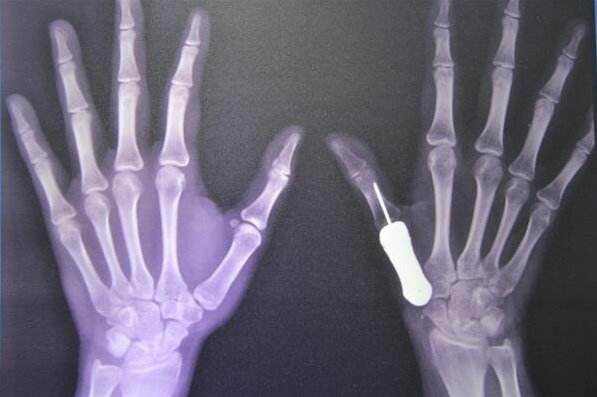

1骨科概念

骨科主要是研究骨骼肌肉系統(tǒng)的解剖、生理和病理的學(xué)科。從治療的角度劃分,骨科醫(yī)療器械可以分為創(chuàng)傷類、脊柱類、關(guān)節(jié)類、足踝類。創(chuàng)傷類是最普遍的,也是最基礎(chǔ)的,其次有脊柱類、關(guān)節(jié)類。

3骨科高值耗材技術(shù)與工藝

理想的骨科植入材料應(yīng)當(dāng)具備優(yōu)良的生物相容性和生物活性。同時(shí),骨科植入材料需要有適宜的機(jī)械和理化性能,有足夠的負(fù)載能力、耐磨損和耐腐蝕性。植入器械的負(fù)載能力及力學(xué)相容性主要與材料的總體性能和結(jié)構(gòu)設(shè)計(jì)等因素有關(guān)。生物活性或相容性、耐磨損和耐腐蝕性則主要取決于材料的表面性能。

3.2材料對(duì)比

目前,常用的骨科植入材料主要有:不銹鋼、鉆合金、鈦合金、氧化鋁、氧化鋯、磷酸鈣鹽、高分子量聚乙烯和碳質(zhì)材料等。